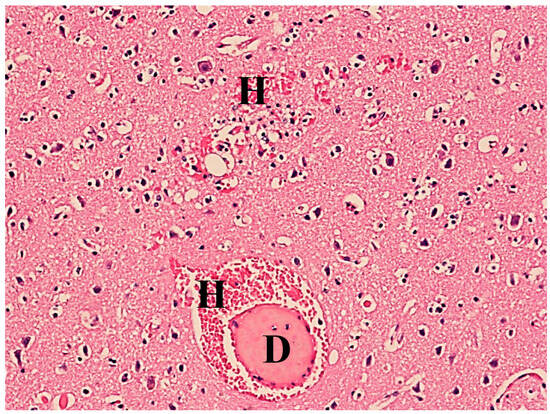

Histopathological examination revealed fat droplets in the alveolar capillaries of the lungs and cerebral blood vessels, and small hemorrhages in the brain tissue (Figure 3).

Figure 3. Brain tissue with signs of acute stasis, fat droplets (D), and small hemorrhages (H). Hematoxylin–eosin stain, 40× magnification.